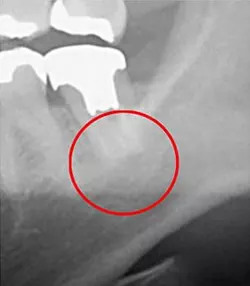

下の画像をご覧ください。

左がレントゲンで、右がCTです。

丸がついている部分が「問題部分」です。違いがお分かりになると思います。レントゲンでは見えない黒い影。CTでははっきり見えています。

レントゲンだと問題なしと診断してしまいます。

これは大問題です!